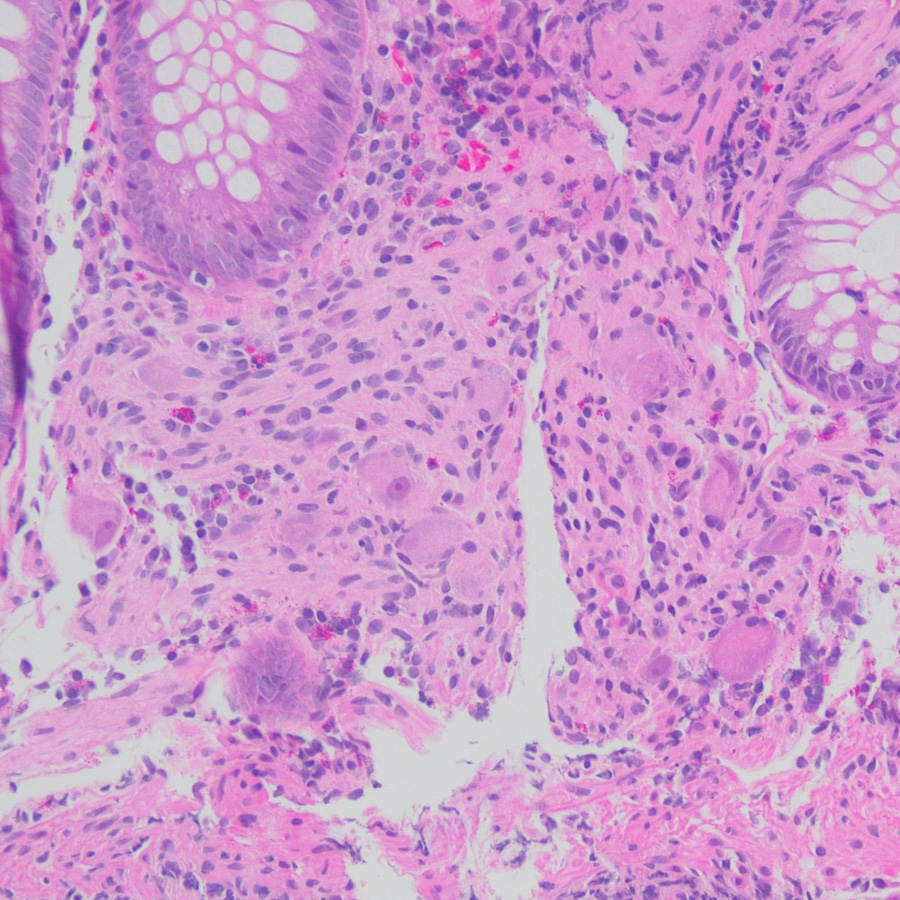

The right colon biopsy shows scattered large cells in the lamina propria with prominent nucleoli and abundant eosinophilic cytoplasm in an otherwise unremarkable colon biopsy (Figures 1-3). These cells are positive for synaptophysin (Figure 4) and negative for CMV by IHC.